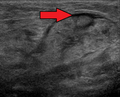

الغدة تحت الفك السفلي إنگليزية: Submandibular gland هي غدة لعابية تقع تحت أرضية الفم. They each weigh about 15 grams and contribute some 60–67% of unstimulated saliva secretion; on stimulation their contribution decreases in proportion as the parotid secretion rises to 50%.[1] The average length of the normal human submandibular salivary gland is approximately 27 mm, while the average width is approximately 14.3 mm.[2]

2. ^ Asai, S.; Okami, K.; Nakamura, N.; Shiraishi, S.; Yamashita, T.; Anar, D.; Matsushita, H.; Miyachi, H. (2012). "Sonographic appearance of the submandibular glands in patients with immunoglobulin G4-related disease". Journal of Ultrasound in Medicine. 31 (3): 489–493. doi:10.7863/jum.2012.31.3.489. PMID 22368140. S2CID 35940244.